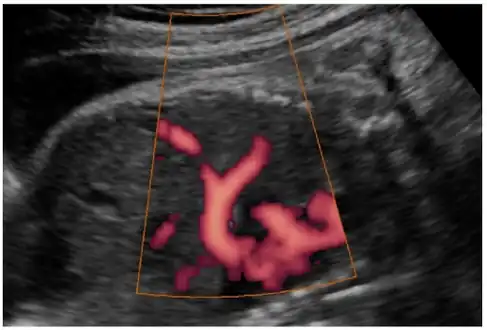

In most cases, postnatal diagnosis is done and up to 2011, only four cases are reported via prenatal diagnosis.[3] Congenital diaphragmatic hernia and intrauterine growth retardation (these two signs put the patients at the risk of afflicting with ring chromosome 15) by fetal ultrasound (Obstetric ultrasonography) at the time period of 16–24 weeks, further investigation and diagnostics (such as karyotyping) must be performed to test the possibility of ring chromosome 15.

- Ultrasound finding in a fetus showing liver herniation into the thorax

- Congenital diaphragmatic hernia